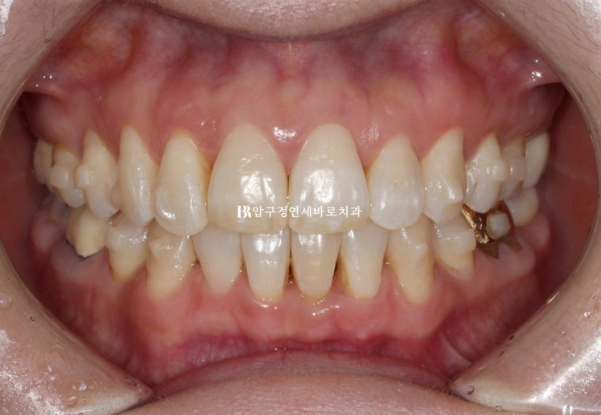

50대 환자분께서 앞니가 점점 뻗치고 틀어져서 교정을 위해 내원하셨습니다.

오래 전 발치교정이 이미 끝났는데 나이가 들면서 점점 앞니가 틀어져서 앞니 부분교정을 위해 오셨습니다.

파란 화살표 부분은 잇몸이 주변치아에 비하여 내려가 있습니다.

그 이유는 배열에서 가장 벗어난 치아여서 입니다.

위 앞니 두개가 튀어나와있고 회전이 되어있습니다.

정식용어는 아니지만 이런 치아를 나비치아 라고 합니다.

이 정도면 인비절라인 라이트로 충분한 교정이 가능합니다.